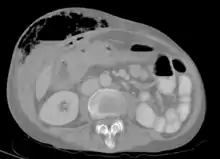

Fistula

Abdominal CT scan with right colocutaneous fistula and associated subcutaneous pneumatosis